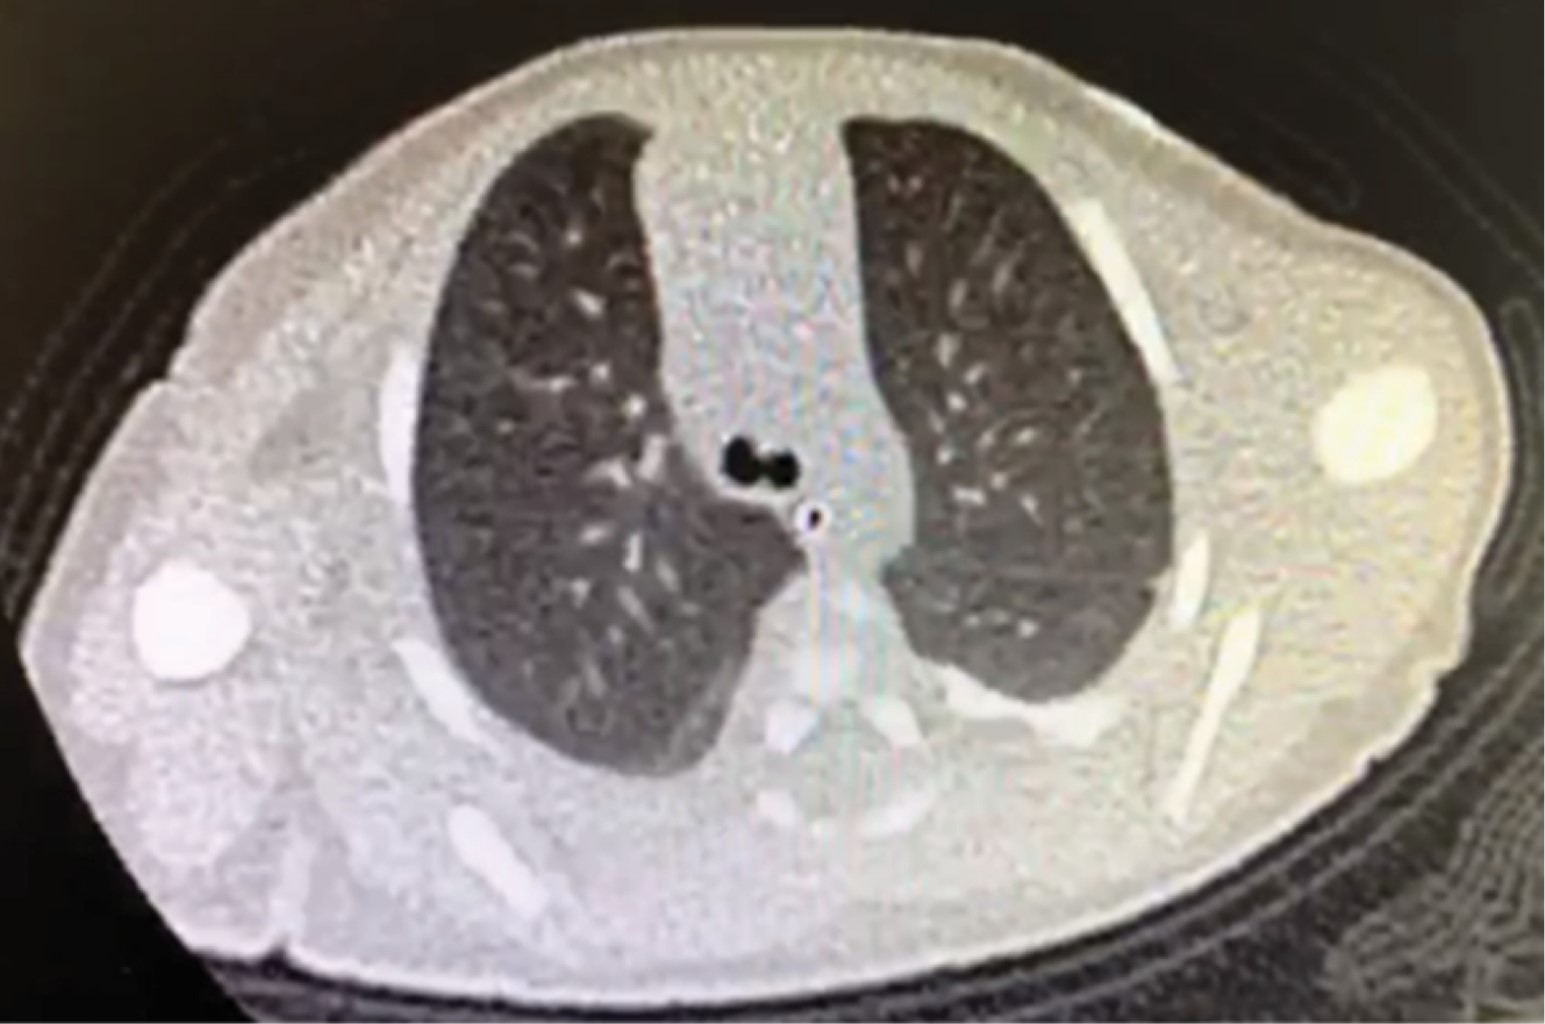

Figure 4